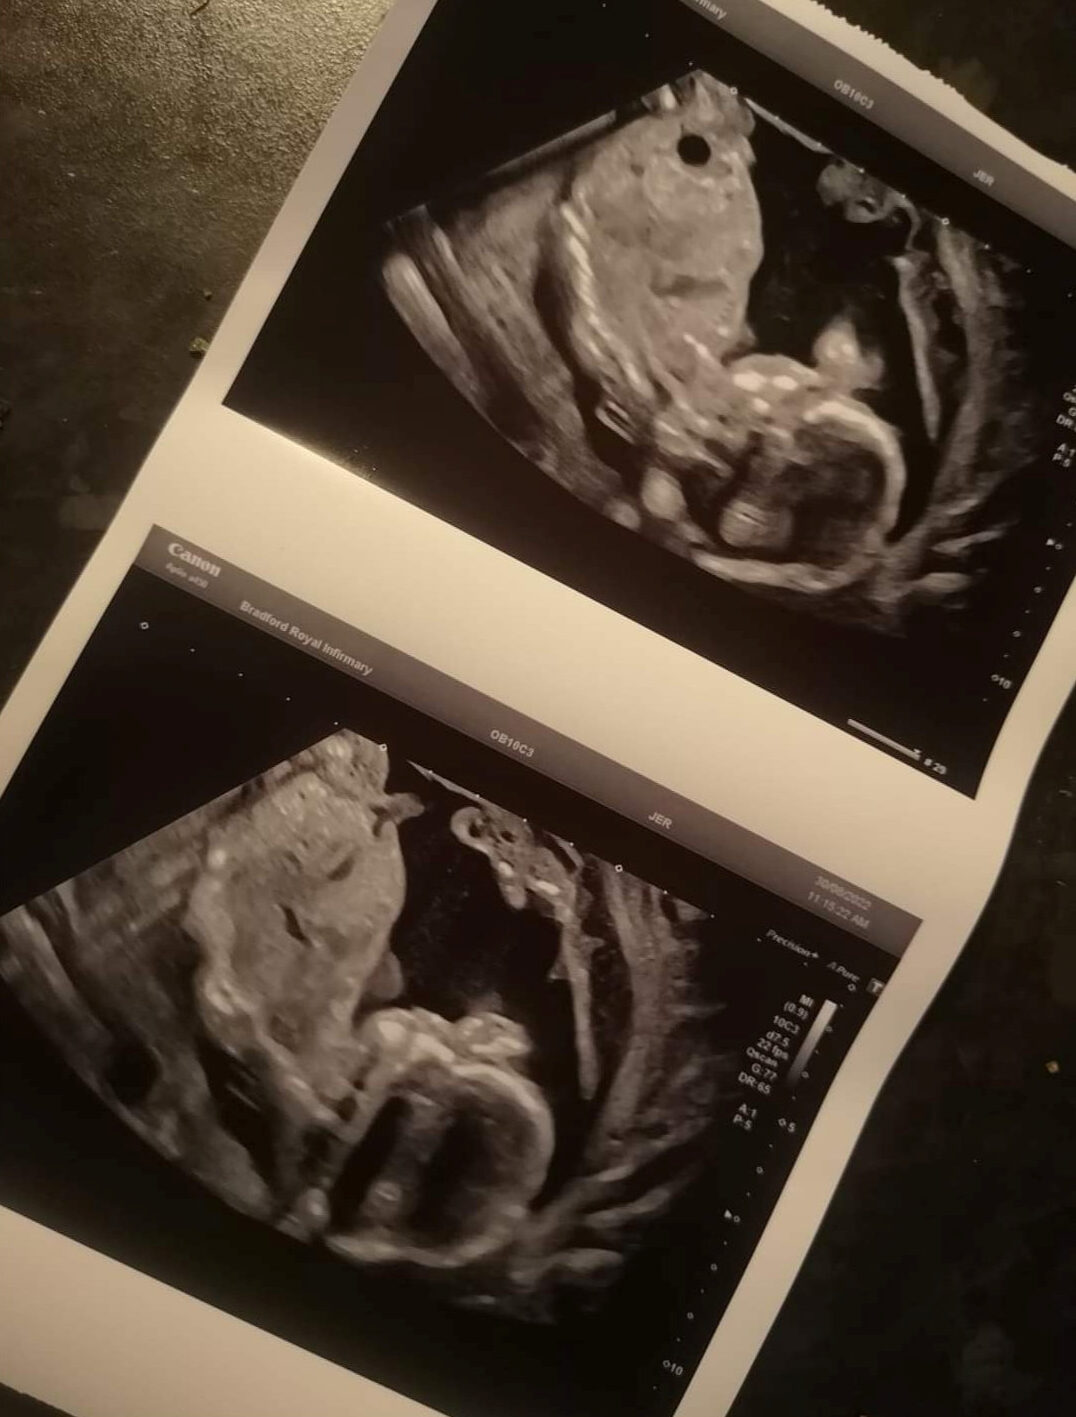

Une maman informée de la mort de son bébé pendant la grossesse, donne naissance à son fils quatre semaines plus tard: «Mon miracle de Noël»

Une maman britannique se réjouit de son bébé miracle de Noël. Le petit est né alors qu’on lui avait annoncé qu’il mourrait dans son utérus.

Hannah Cole, 27 ans, originaire de Wibsey, dans le West Yorkshire (Angleterre), a été admise à l’infirmerie royale de Bradford (BRI), dans le West Yorkshire, après avoir perdu les eaux au bout de 20 semaines. Le lendemain, comme les médecins ne détectaient aucun battement de cœur, Hannah a été informée du décès de son bébé et a dû se soumettre à un accouchement provoqué.

Cependant, Hannah Cole sentait en son for intérieur que son fils était encore en vie et a demandé au personnel de l’hôpital de procéder à un second scanner – qui a permis de détecter un battement de cœur.